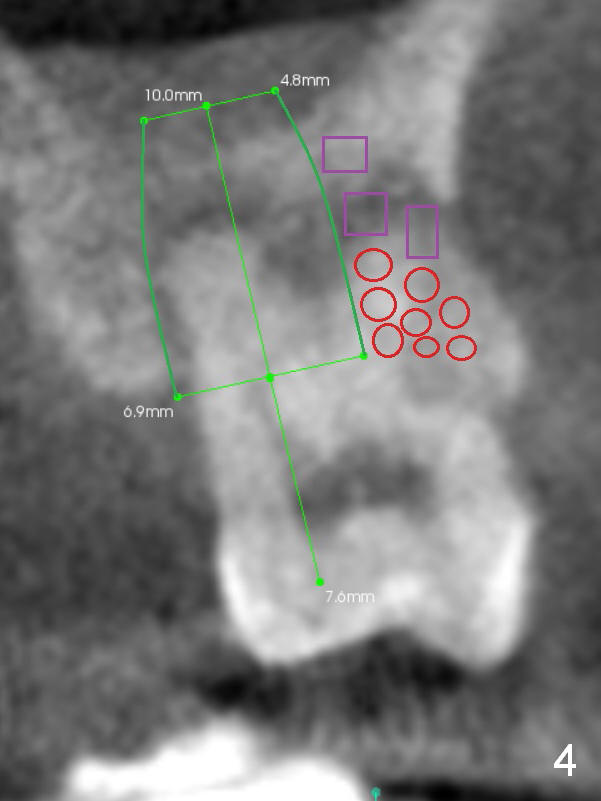

A 42-year-old lady (HJ) has advanced periodontitis at #15 (Fig.1 (CBCT sagittal section)). The buccal (B) plate is thin (Fig. 2 (coronal section), 3 (axial section)). The apical bone is also thin (Fig.1,2). A 7x10 mm implant is placed in a position so that the implant contacts the mesial, palatal and distal walls of the socket (treated with 2% Xylocaine with 1:50,000 Epinephrine) for primary stability (Fig.3). The buccal gap will be filled with Osteogen Plug apically (Fig.4 purple rectangles) and bone graft coronally (red circles). SM implant (Fig.4) is more tapered than UF one (Fig.2), easier to insert.

Open Sinus Master Kit and use 2.8 and 3.6 mm round burs at 2 mm depth to start osteotomy, followed by 4.5-6x14 mm Tatum tapered taps at 11 mm and SM or UF 6.5 mm tap. If stability of the last tap is low, insert a 7 mm implant. If the Sinus Master Kit does not work, try RT2-4. Draw blood after extraction confirms buccal wall defect. Place PRF before Osteogen Plug and bone graft (Fig.4' yellow curved line).